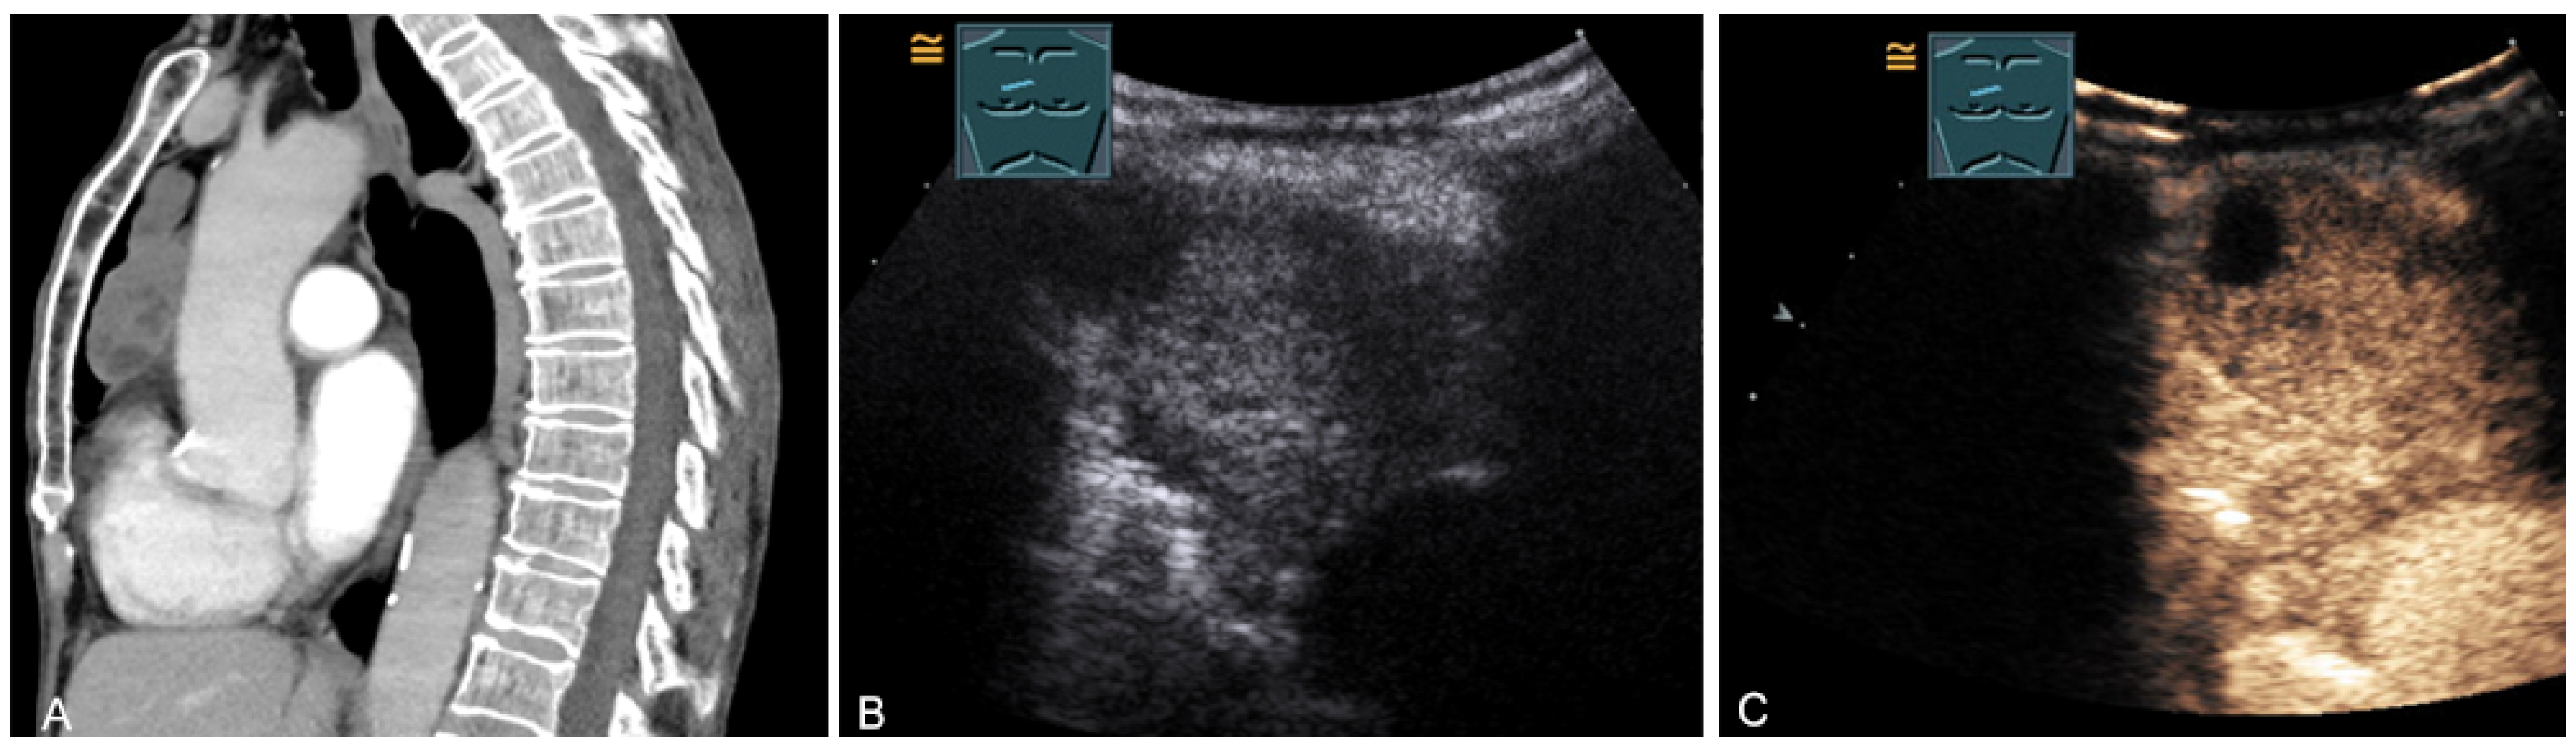

Figure 23.

A patient, with a history of germ cell tumor, with tumor formation in the anterior mediastinum on CT (provided by Prof. Dr. Andreas H. Mahnken, Marburg, Germany) (A), B-mode US (B), and CEUS (C), confirmed by biopsy as mediastinal metastasis of malignant teratoma.

Malignant tumors of the thymus may have irregular borders with infiltrative growth, chaotic vascularization, cystic areas, or necrotic components on B-mode US, CDS, and CEUS [28,36,37]. These features can be used to evaluate the malignancy of the masses in the mediastinum. However, the definitive diagnosis is basically made by histological confirmation. More frequently, primary central bronchial carcinomas grow infiltrating directly into the anterior mediastinum and can be sonographically visualized in the case of pleural contact and, therefore, can also undergo US-guided biopsy (Figure 24).